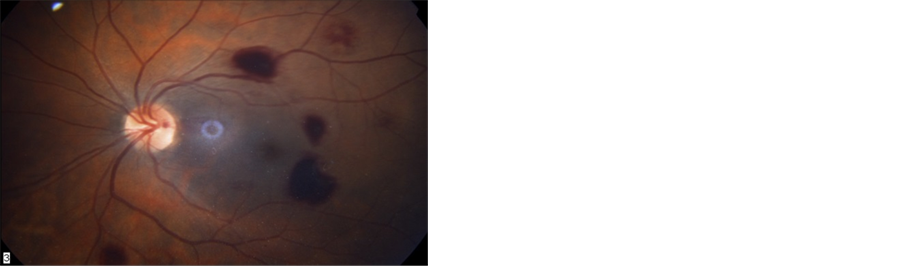

Figure 3. Fundoscopic examination four days after revascularization. Multiple retinal hemorrhages are demonstrated in both eyes (a). Three weeks later most hemorrhages have been absorbed (b).